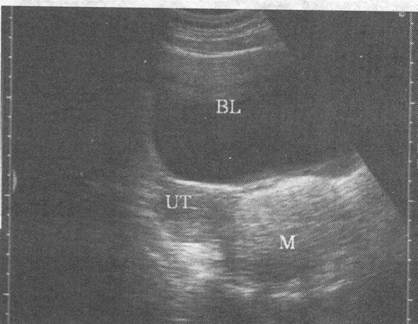

如图,女,26岁,无明显不适,盆腔横断面,最可能的诊断是( )。

[单选题]如图,女,26岁,无明显不适,盆腔横断面,最可能的诊断是( )。A.炎性包块B.宫外孕C.畸胎瘤D.黄体囊肿E.正常声像图

[单选题]如图,女性,26岁,无明显不适,盆腔横断面,最可能的诊断是()A.炎性包块B.宫外孕C.畸胎瘤D.黄体囊肿E.正常声像图

[单选题]如图,女性,25岁,无明显自觉症状,盆腔横断面,最可能的诊断是A.附件区炎性包块B.异位妊娠C.畸胎瘤D.黄体囊肿E.正常声像图

如图,女,26岁,无明显不适,盆腔横断面,最可能的诊断是

[单选题]如图,女,26岁,无明显不适,盆腔横断面,最可能的诊断是A.炎性包块B.宫外孕C.畸胎瘤D.黄体囊肿E.正常声像图